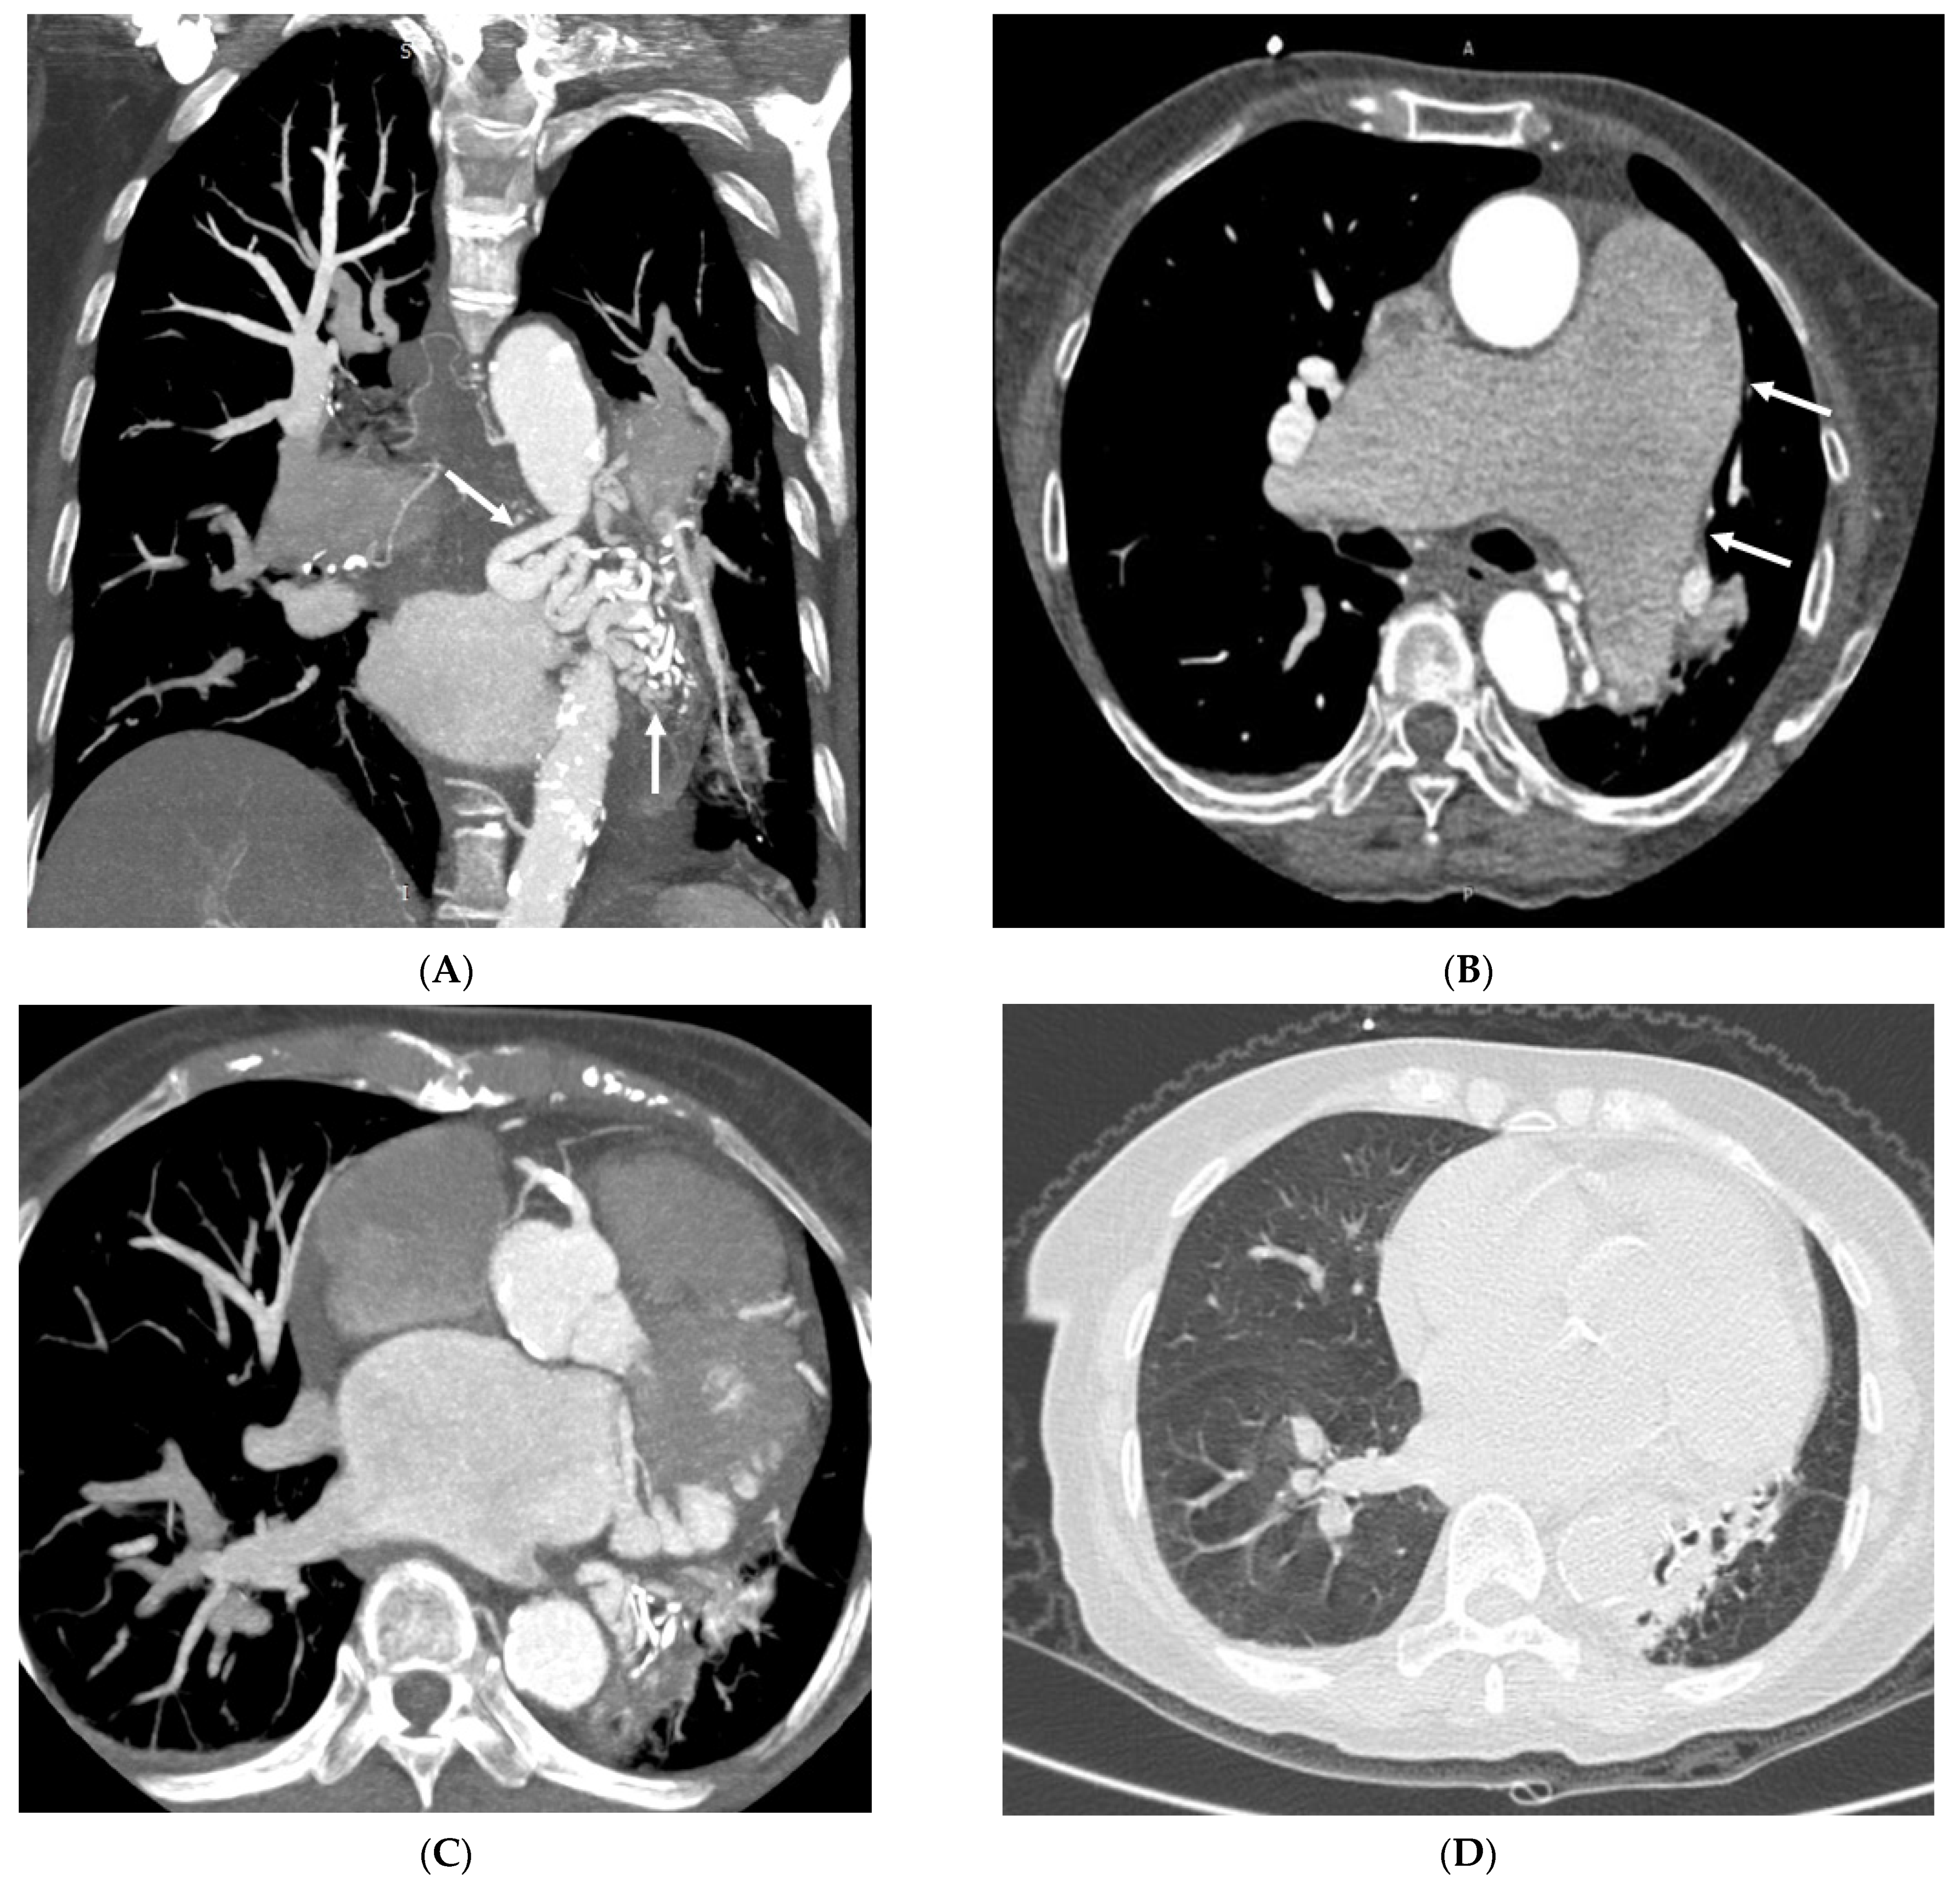

3.2. Imaging Appearances of CTPA